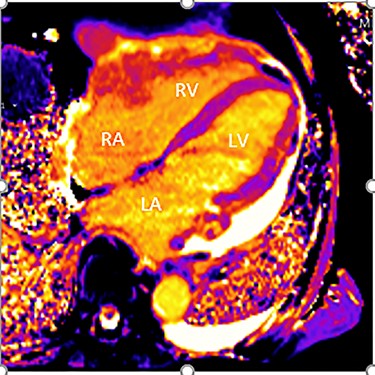

Further staging imaging was recommended by the radiology team. A CT head scan demonstrated no abnormalities, whereas CT chest–abdomen–pelvis (CAP) found significantly enlarged necrotic mediastinal lymph nodes with invasion into the pericardium and heart; bilateral adrenal nodules (suspicious for metastases) and appearances consistent with a lymphoproliferative disorder. The testicular biopsy found large lymphocytes with abundant cytoplasm and prominent nucleoli consistent with a diffuse large B-cell lymphoma (DLBCL). A positron emission tomography (PET) scan was organized at the request of the oncology team (Figs 4 and 5).

PET scan (transverse plane) demonstrating an enhancing lesion encroaching the heart with necrotic lymph nodes.

PET scan (coronal plane) showing intensely metabolically active lymphadenopathy on both sides with extra-nodal involvement through lymphoid tissue, adrenals and muscle.

He was subsequently diagnosed with stage IV (Lugano) DLBCL and underwent the R-CHOP chemotherapy regimen. He has responded well to his oncological treatment.